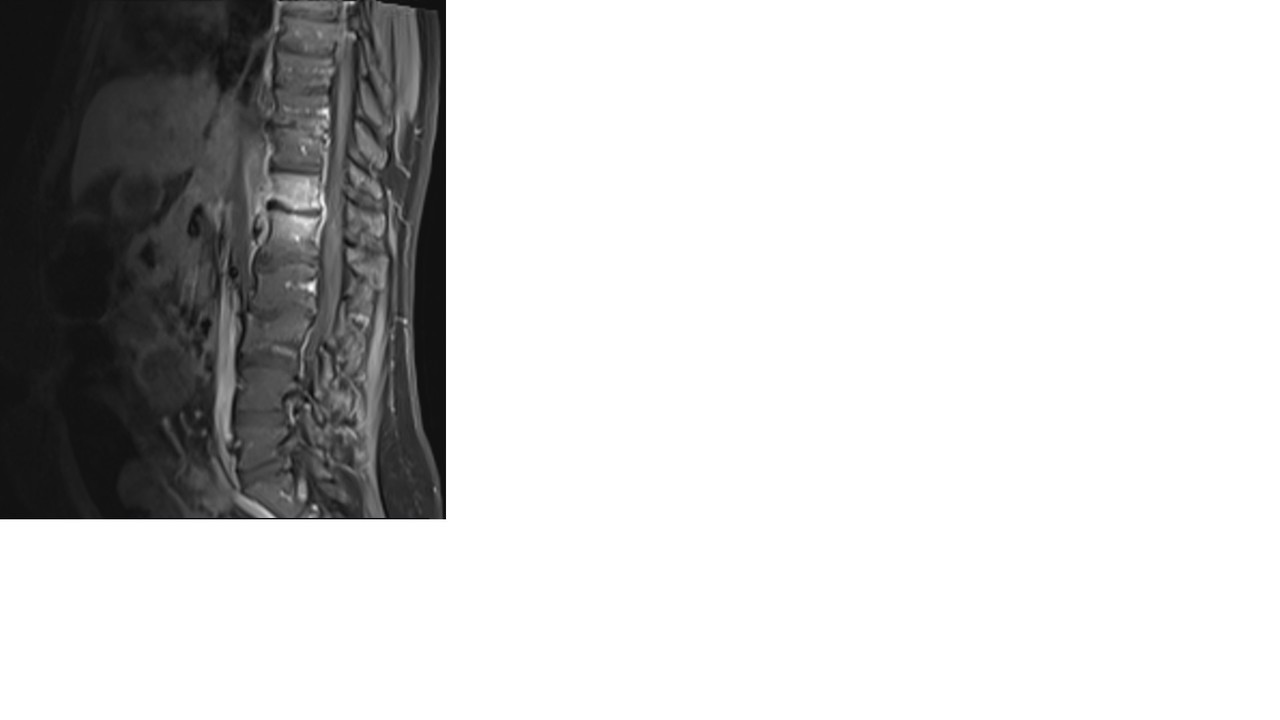

Une imagerie est réalisée, présentée ci-dessous (figure 4) :

Voici une séquence d’IRM séquence T2 STIR, puis T1 avec injection de gadolinium (figures 4 et 5).

L’IRM réalisée retrouve :

– épaississement des parties molles prérachidiennes en regard de T12/L1 ;

– présence d’un hypersignal STIR, hyposignal T1, se rehaussant après injection du plateau supérieur de L1 et du plateau inférieur de T12, en miroir associé à un abcès du muscle psoas gauche mesurant 10 x 11 mm dans un plan axial et près de 3 cm de hauteur ;

– présence d’une épidurite infectieuse millimétrique prédominant en région paramédiane et foraminale gauche venant au contact du sac dural et probable retentissement sur la racine T12 gauche dans sa portion foraminale ;

– absence d’anomalie formelle de signal du disque T12-L1 ;

– pas d’anomalie de signal visible du cône terminal et des racines de la queue de cheval ;

– deuxième foyer de spondylodiscite débutante sur le versant postérieur en T10/T11 avec rehaussement disco-vertébral, ainsi que spondylite très localisée du plateau inférieur de L3 ;

– pas de sténose foraminale ou anomalie discale significative visible aux étages sous-jacents (déformation sinueuse de l’espace intersomatique L2-L3 d’allure ancienne).